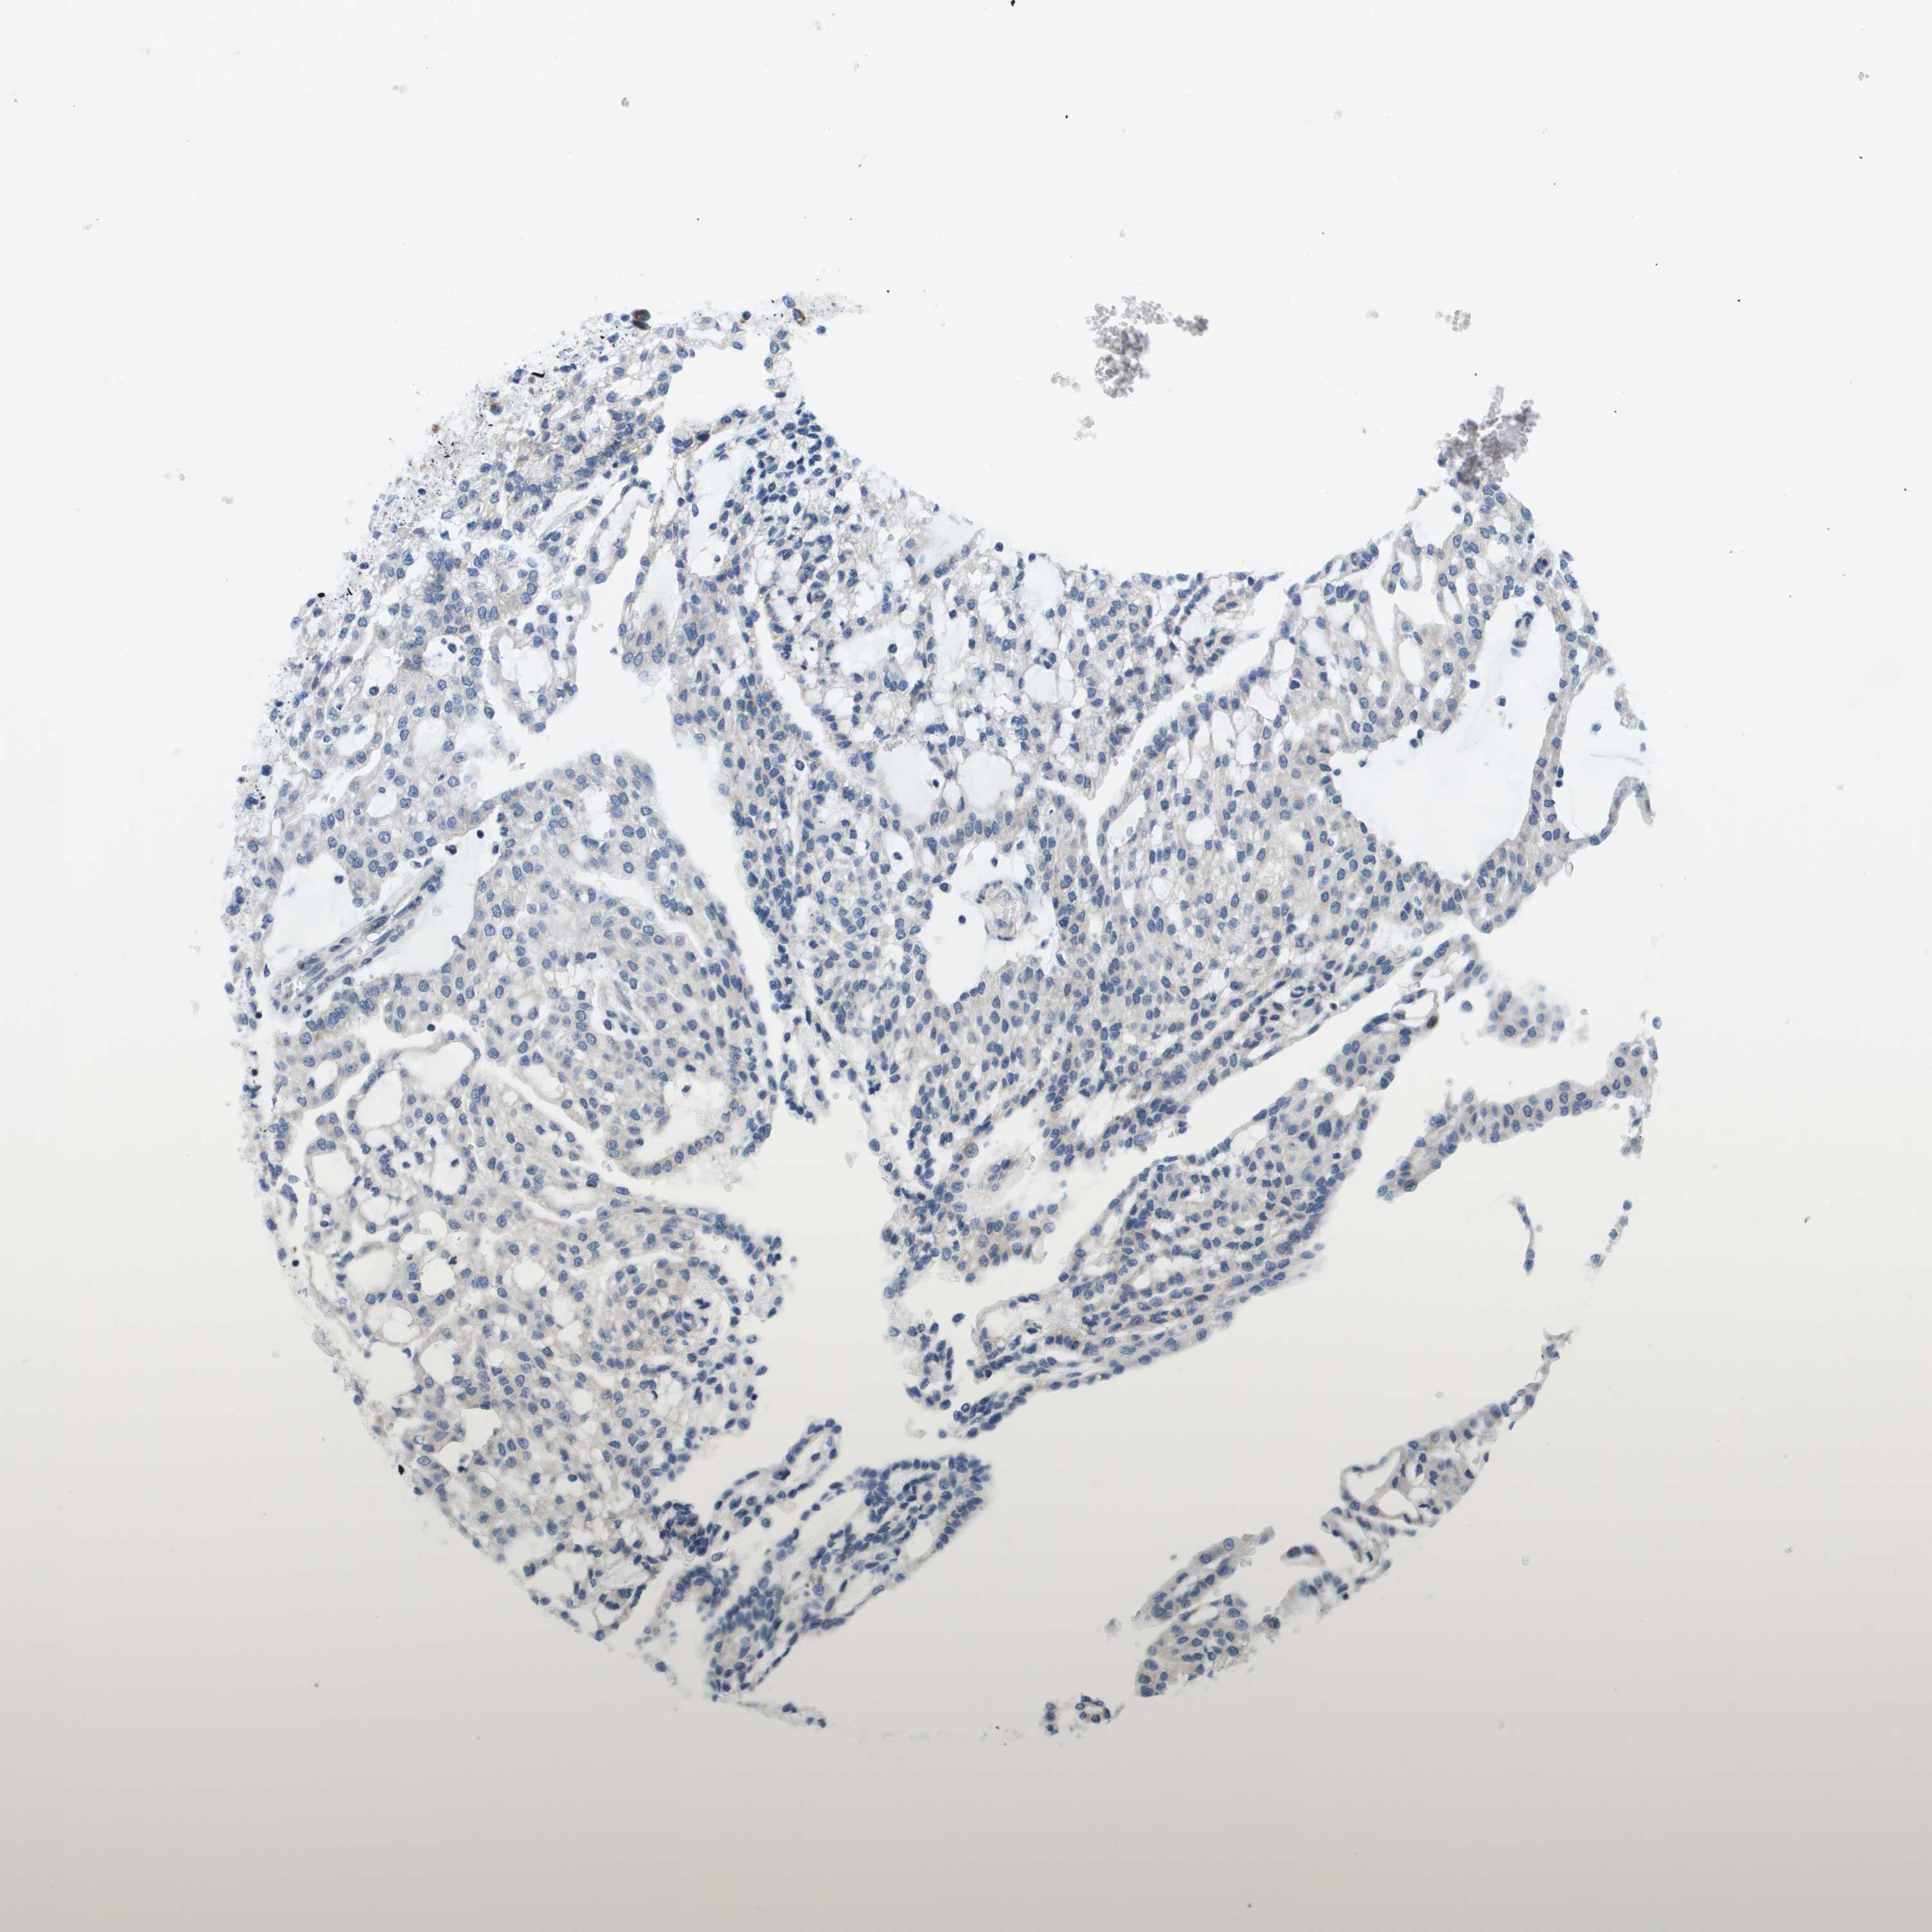

KIDNEY RENAL PAPILLARY CELL CARCINOMA (TCGA) - Interactive survival scatter ploti

The Survival Scatter plot shows the clinical status (i.e. dead or alive) for all individuals in the patient cohort, based on the same data that underlies the corresponding Kaplan-Meier plots. Patients that are alive at last time for follow-up are shown in blue and patients who have died during the study are shown in red.

The x-axis shows the expression levels (FPKM) of the investigated gene in the tumor tissue at the time of diagnosis. The y-axis shows the follow-up time after diagnosis (years). Both axes are complimented with kernel density curves demonstrating the data density over the axes. The top density plot shows the expression levels (FPKM) distribution among dead (red) and alive patients (blue). The right density plot shows the data density of the survived years of dead patients with high and low expression levels respectively, stratified using the cutoff indicated by the vertical dashed line through the Survival Scatter plot. This cutoff is automatically defined based on the FPKM cutoff that minimizes the p-score. The cutoff can be changed by dragging the vertical line or by entering a cutoff value in the square labeled "Current cut-off".

Under the Survival Scatter plot the p-score landscape (black curve; left axis) is shown together with dead median separation (red curve; right axis). Dead median separation is the difference in median mRNA expression between patients who have died with high and low expression, respectively. It is calculated as follows: median FPKM expression of dead patients with high expression - median FPKM expression of dead patients with low expression. This is intended to aid the user in visually exploring custom cutoffs and the associated p-scores and dead median separation.

Individual patient data is displayed and can be filtered by clicking on one or more of the category buttons on the top of the page. Categories describing expression level and patient information include: high, low, alive, dead, female, male and tumor stages. The scale of the x-axis can be toggled between linear and log-scale by clicking on the "x log" button. Mouse-over function shows TCGA ID, patient information and mRNA expression (FPKM) for each patient.

& Survival analysisi

Kaplan-Meier plots summarize results from analysis of correlation between mRNA expression level and patient survival. Patients were divided based on level of expression into one of the two groups "low" (under cut off) or "high" (over cut off). X-axis shows time for survival (years) and y-axis shows the probability of survival, where 1.0 corresponds to 100 percent.

KRT23 is not prognostic in Kidney Renal Papillary Cell Carcinoma (TCGA)

TCGA RNA samplesi

RNA-seq data is reported as average FPKM (number Fragments Per Kilobase of exon per Million reads), generated by the The Cancer Genome Atlas (TCGA) .

Normal distribution across the dataset is visualized with box plots, shown as median and 25th and 75th percentiles. Points are displayed as outliers if they are above or below 1.5 times the interquartile range. FPKM values of the individual samples are presented next to the box plot.

Average pTPM 2.4

Number of samples 282